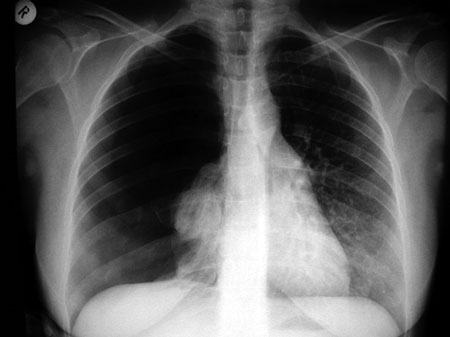

Εικόνα 4

Εικόνα 4. Ηλεκτροκαρδιογράφημα την 4η μετεγχειρητική ημέρα Π εντός των φυσιολογικών ορίων.

Μετά από δύο ημέρες αποφασίστηκε η αφαίρεση της θωρακικής παροχέτευσης από τον ειδικό θωρακοχειρουργό. Όμως, κατά τον κλινικό και ακτινολογικό έλεγχο της επομένης ημέρας εμφανίστηκε υποτροπή του πνευμοθώρακα και έτσι επανατοποθετήθηκε η θωρακική παροχέτευση. Μετά από δύο ημέρες επιχειρήθηκε εκ νέου η αφαίρεση της παροχέτευσης, η οποία όμως δεν ήταν εφικτή, γιατί ο πνευμοθώρακας υποτροπίασε. Στον καρδιολογικό έλεγχο (με τη θωρακική παροχέτευση σε λειτουργία) το ΗΚΓ παρουσίαζε σαφή μεταβολή: ΚΣ=60/λεπτό, τα αρνητικά «Τ» δεν υπήρχαν, ενώ τα επάρματα «R» στις απαγωγές ΙΙΙ και V5 είχαν μικρύνει (εικόνα 3), στοιχεία που είναι συμβατά με τη μείωση του πνευμοθώρακα σε σύγκριση με αυτόν της εισόδου.